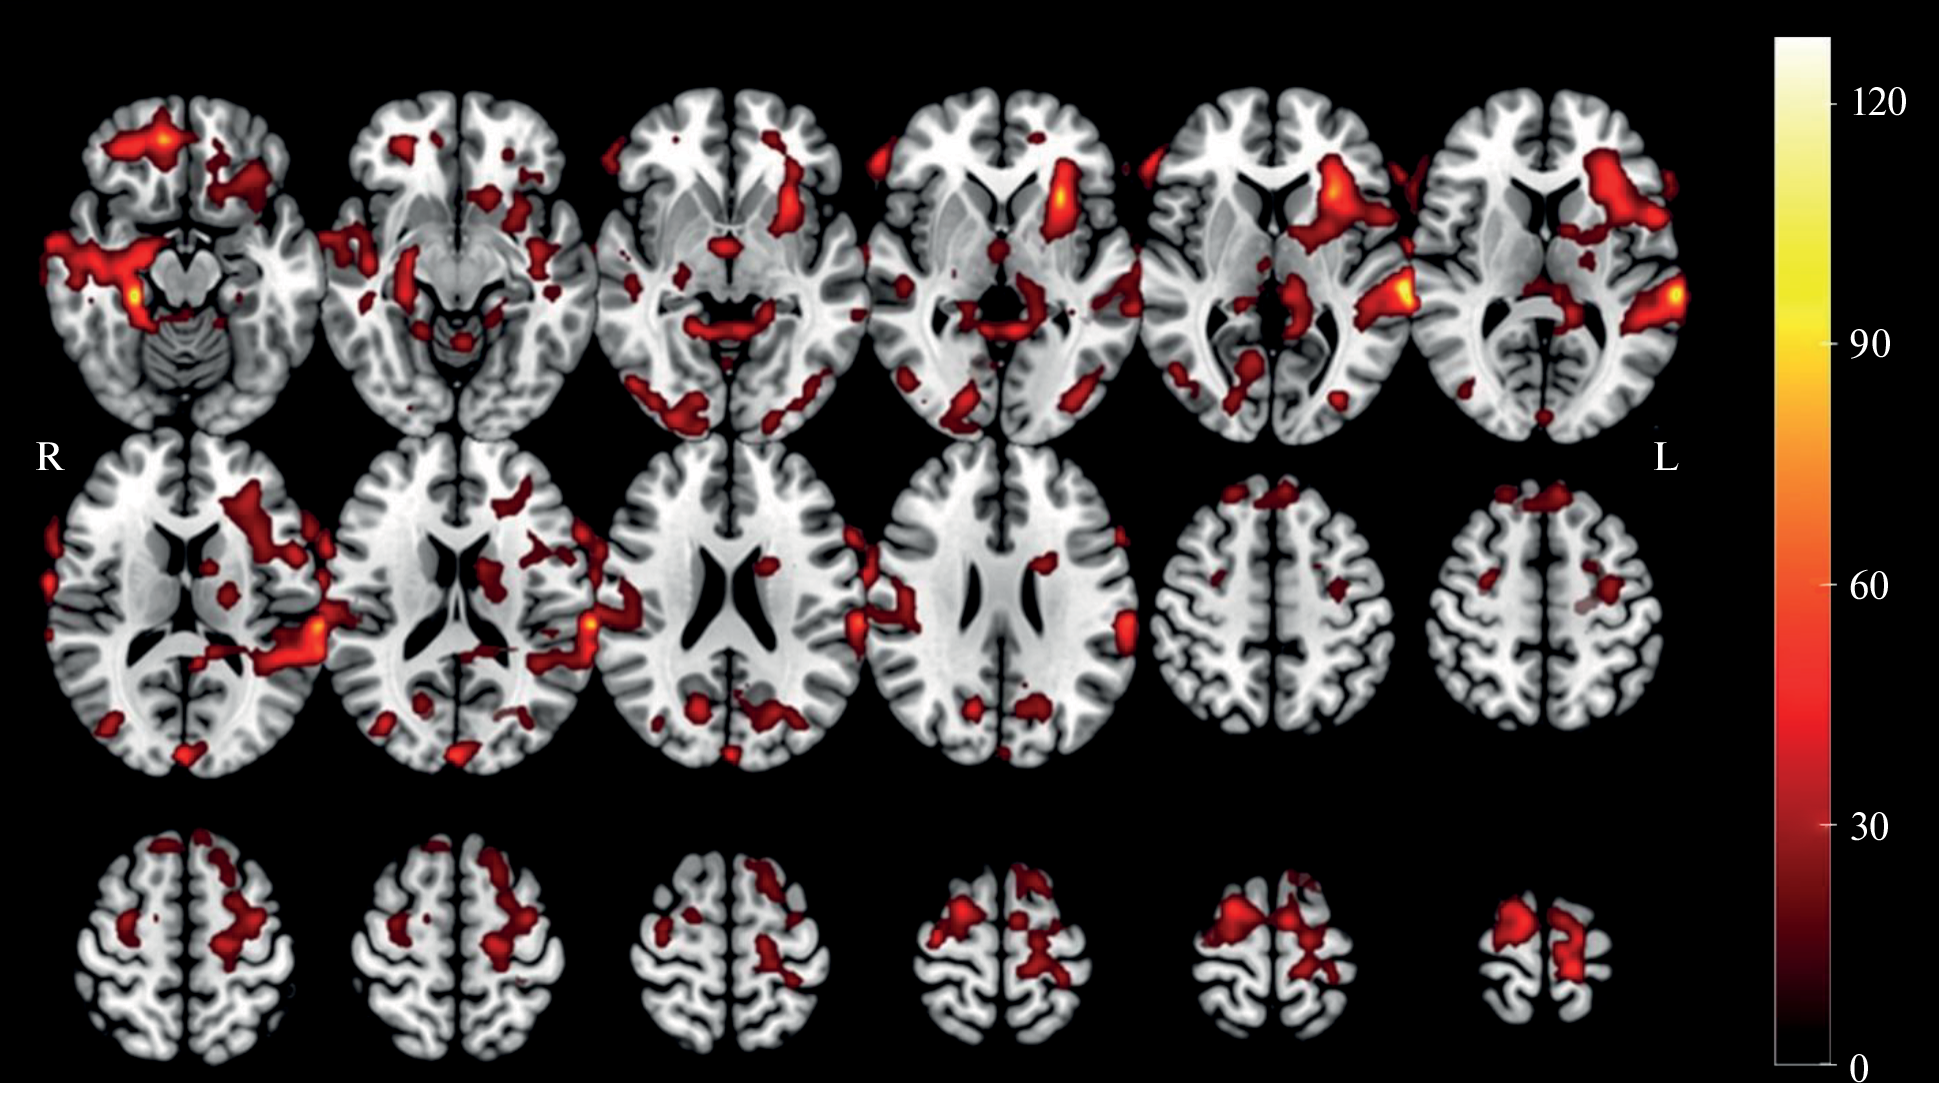

A group of 20 healthy subjects (11 males and 9 females) performed a selective auditory attention task in a dichotic listening paradigm with different levels of perceptual load. Analysis of brain activation patterns measured with fMRI during selective listening to fusion speech with distractors of varying strengths revealed statistically significant sex differences in the topography of cortical activity. “Female > male” effects dominated in the left superior temporal gyrus and the left pre and postcentral gyrus; while the most pronounced “male > female” effects were found in the left islet, shell and frontal lobule. Statistically significant effects were also obtained by comparing activation patterns according to the level of task complexity: It was shown that masking with a female speaker’s voice caused greater activation of additional high-level information processing areas. The findings indicate the presence of sexual dimorphism in the organization of the selective auditory attention system.